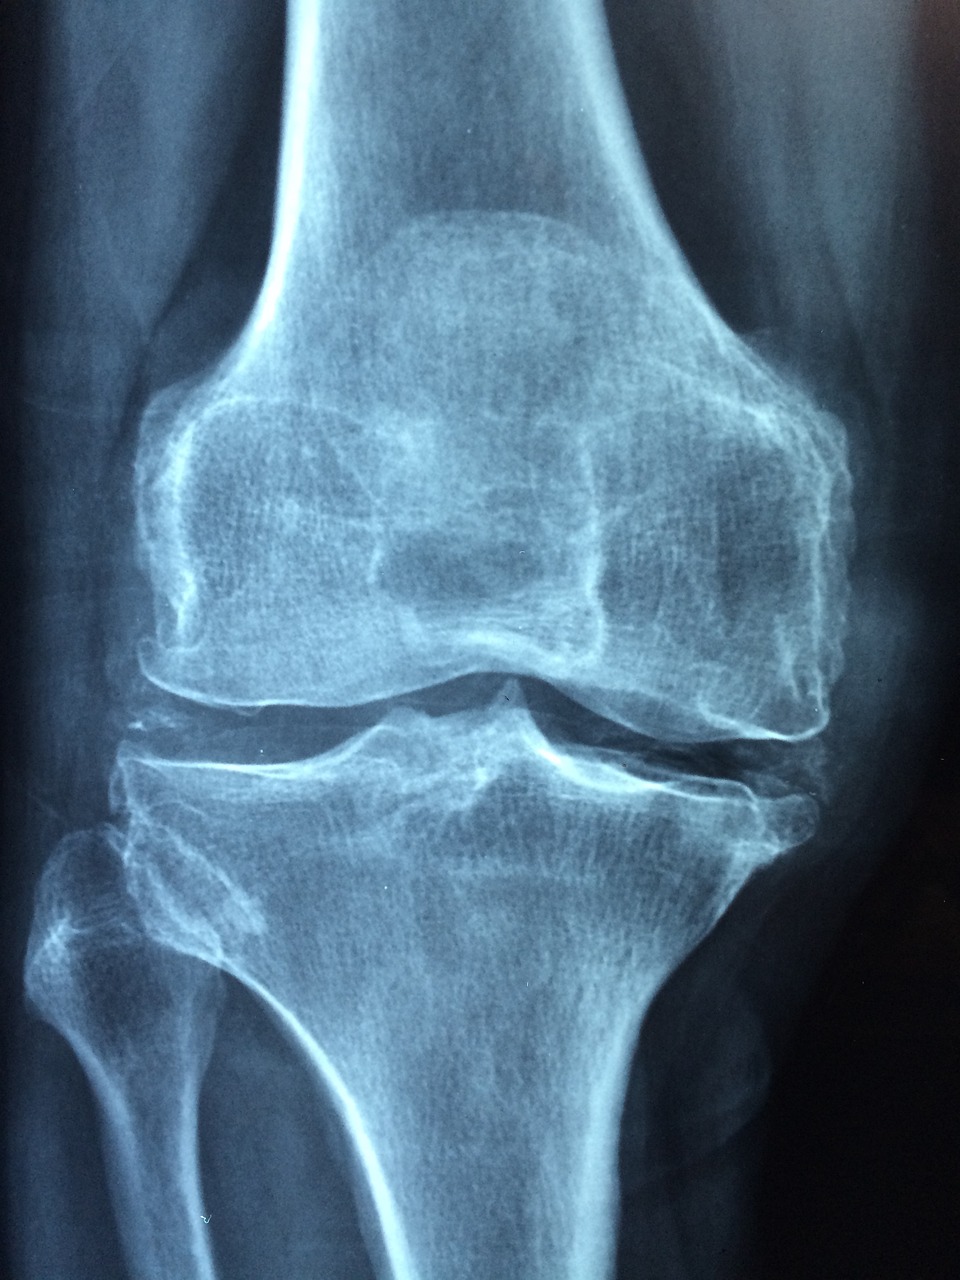

위에서 이야기한 것처럼 파골세포를 억제하는 기능이 있습니다. 인체는 노화가 지속될수록 골아세포보다는 파골세포의 활동이 더 활발하게 됩니다. 갱년기를 넘어가는 나이부터 생기는 골다공증도 이것이 원인입니다. MBP는 이러한 파골세포의 활동을 억제하여 골다공증을 예방하는데 도움이 됩니다.

파골세포의 활동을 억제하는 만큼 골아세포의 활동은 증가시킵니다. 이는 골밀도와 강도를 개선시킵니다. 그렇기에 골다공증을 예방하고 뼈를 더 튼튼하게 만드는데 도움이 됩니다.

뼈 건강이 악화되면 아무래도 관절에 부하가 있을 것입니다. 약해진 뼈를 관절들이 지탱해주어야 하기 때문이죠. 그렇기에 나이가들면 골다공증뿐만 아니라 관절염도 무섭습니다. MBP는 뼈를 튼튼하게 하여 관절의 부담을 줄여주고 MBP의 생리활성물질이 염증을 감소시켜 주는 효능이 있어 관절염과 같은 염증성 질환에도 도움이 됩니다.